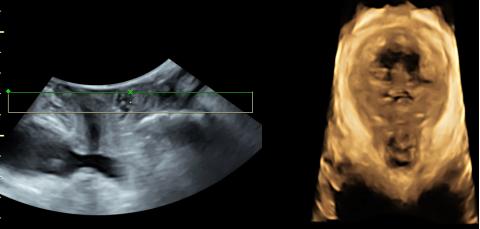

超越GE传统的HDlive成像模式,借助强大的GPU的处理能力,增加了组织透明度调节,实现100级可调,从内到外,一览无余。带来容积图像更强的边界感与距离感。煊影成像技术在早孕、双胎等评估有良好优势。

基于全新煊光平台强大的数据处理能力与效率,GE得以将原Voluson 平台上的HDlive技术与HD Flow技术相结合,不仅得到了三维血管栩栩如生的显示,更是在微小血管成像上更加敏锐、可靠。该技术对于深部小血管的立体结构显示极具优势,在评估血管分布或灌注状态时,如同采用血管造影模式。

独有的煊影成像(HDlive Silhouette)和煊流技术(HDlive Flow),给容积超声带来出色的分辨率。胎儿识别追踪技术(SonoRenderlive)简化了胎儿表面成像,对于早孕的评估极有优势。